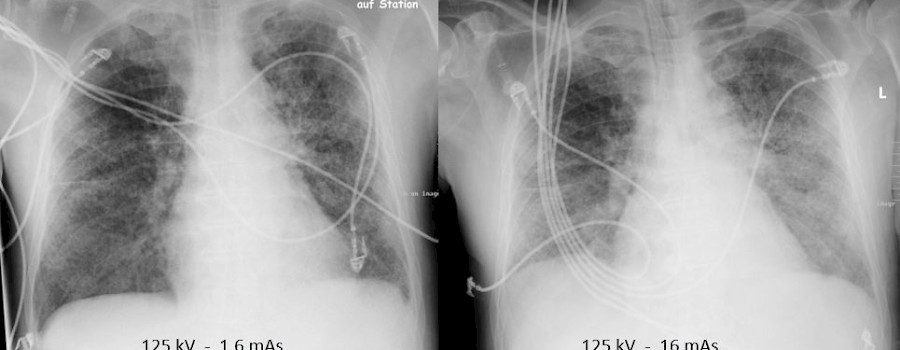

Die Etablierung digitaler Röntgenverfahren hat zu einem veränderten Umgang mit der Strahlendosis geführt. Dieser Umgang ist noch verbesserungswürdig.